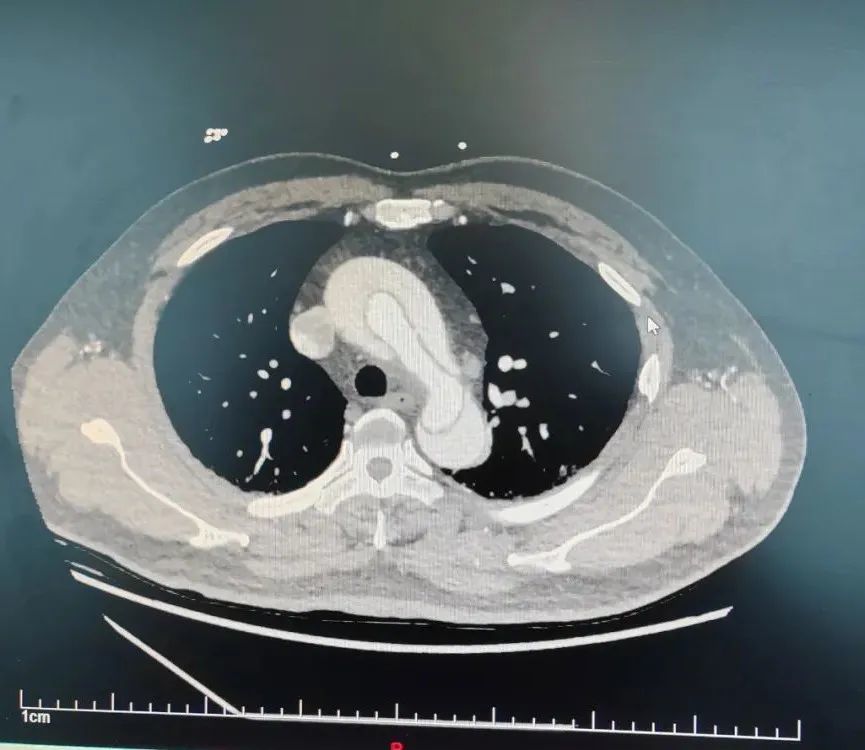

术前cta提示胸主动脉夹层,红色箭头示主动脉撕裂的内膜片.通讯员供图